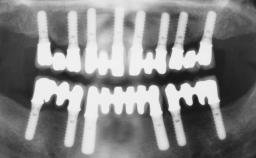

Immediate Loading of Six Implants in the Maxilla and Final Restoration with a Full-Arch Gold/Ceramic FDP Involving the Concept of Tilted Implants

A 61-year-old male patient with a failing fixed maxillary rehabilitation and a fixed mandibular rehabilitation requested a new fixed maxillary rehabilitation. The patient was wearing a temporary metal-reinforced maxillary bridge inserted two years before the consultation. He reported that his previous dentist did not want to insert a definitive framework because he considered the residual teeth to have a negative prognosis. The patient reported a history of recurrent caries and endodontic complications as the main reason for the previous extractions. The anamnesis was negative for periodontal disease and bruxism. The patient’s chief compliant was the mobility of his maxillary prosthesis, which needed to be re-cemented frequently, and discomfort during chewing.Moreover, the patient was not satisfied with the esthetic appearance of his maxillary teeth, which he found too long. The patient asked for a stable and comfortable fixed maxillary rehabilitation and firmly rejected any removable solution.

# of Implants 6

Type of Implants One-Piece|Reduced-Diameter

Prosthesis Type FDP

Bone Volume Deficient horizontally, allowing simultaneous augumentation